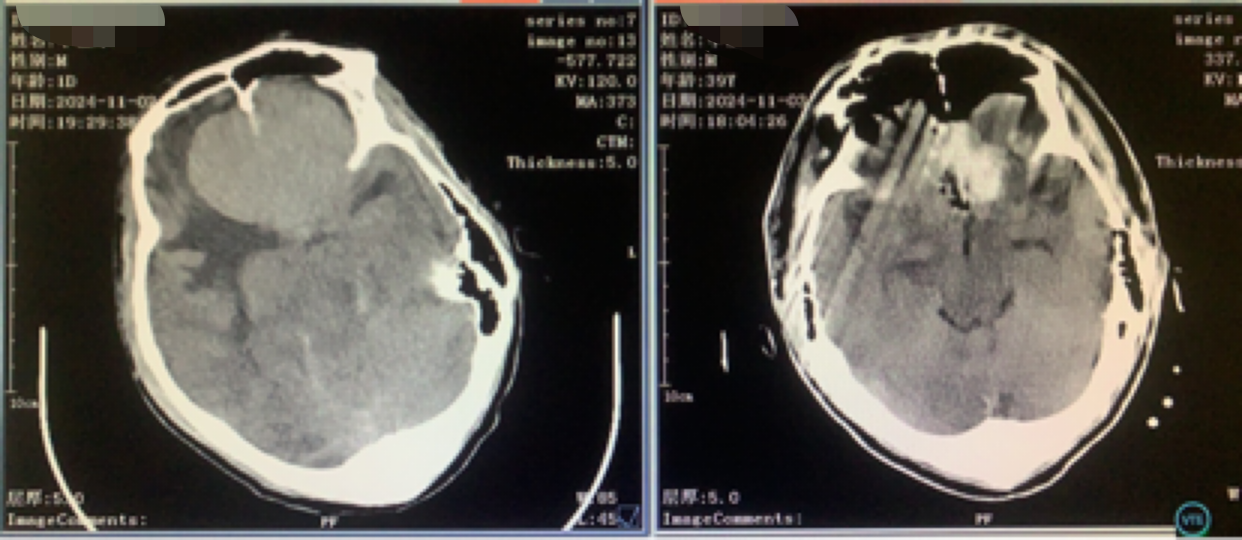

术前CT

神志昏迷双瞳散大对光反射迟钝入院,入院后甘露醇脱水加地米静滴后患者神经功能有改善,能摸索定位,瞳孔反射改善。考虑占位大直接切除可能出血多,拟术前栓塞处理,但造影发现栓塞不易风险高后放弃栓塞。